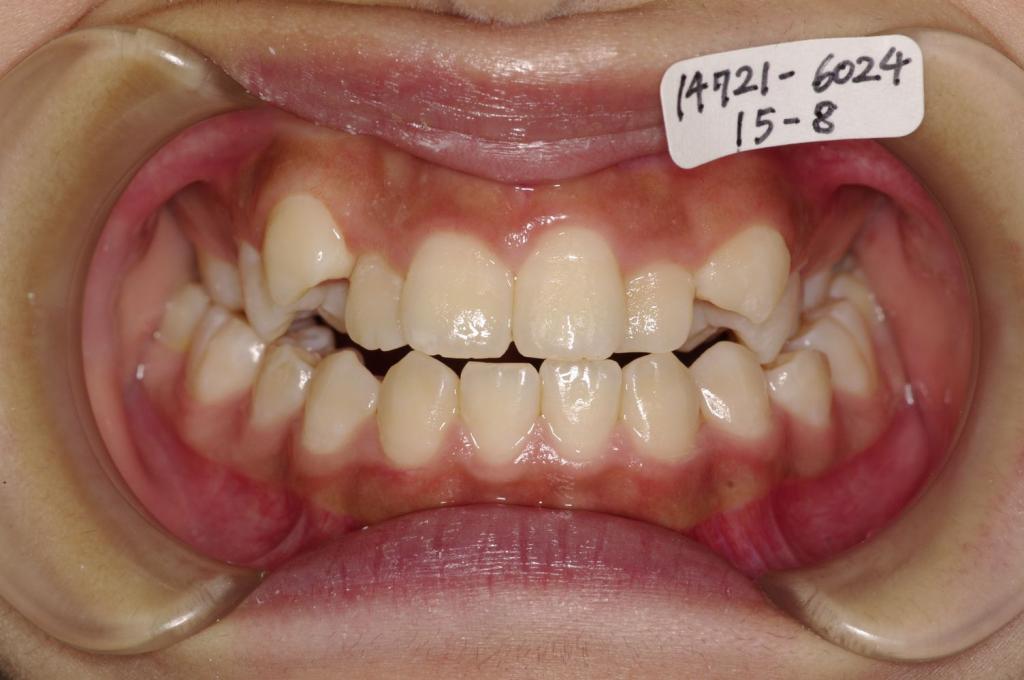

歯欠損の矯正治療

(治療期間、治療前後写真、治療方法、費用)WORKS